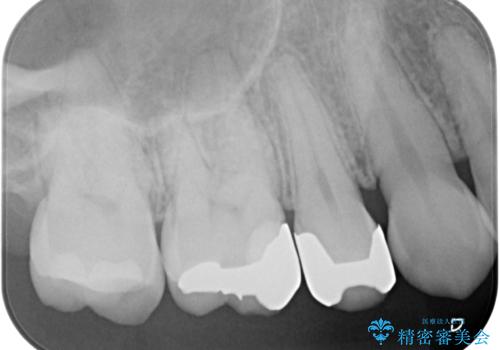

- 銀歯をやり替えたいとのことで来院された患者様です。金属の詰め物の大きさ、虫歯の範囲を考慮してセラミックの詰め物(セラミックインレー)で治療を行っていくことにしました。

拡大鏡視野下で、金属の詰め物(メタルインレー)、虫歯の除去を行い、セラミックインレーに適した形に整えました。

手前の銀歯は患者様のご希望によりやり替えをしていません。